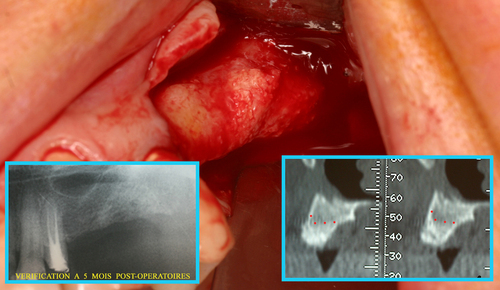

Cela permet d’envisager immédiatement une régénération osseuse qui est effectuée le jour même des extractions et le résultat à 5 mois postopératoires (fig.31) montre une régénération complète du massif osseux.

Fig. 31

Régénération osseuse du maxillaire